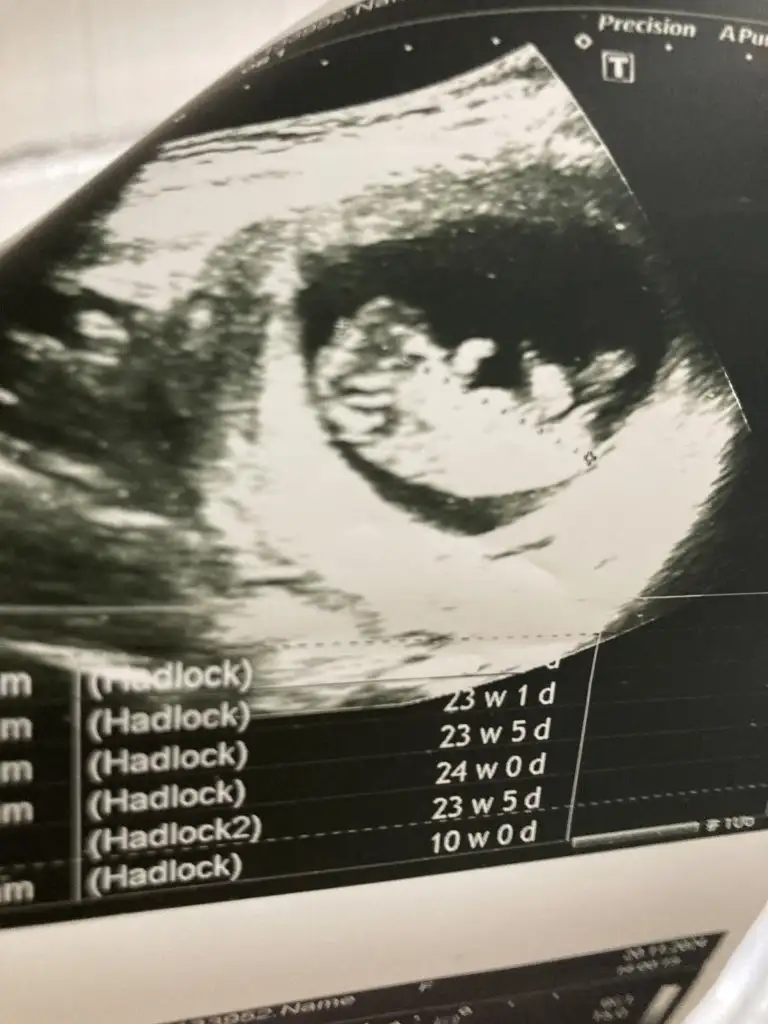

Merhaba 10 haftalık cinsiyet tahmini yapabilir misiniz rica etsem